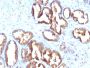

Recognizes a protein of 52 kDa, identified as prostate specific acid phosphatase (PSAP). This enzyme catalyzes the conversion of orthophosphoric monoester to alcohol and orthophosphate. It is synthesized under androgen regulation and is secreted by the epithelial cells of the prostate gland. PSAP is found in non-neoplastic adult and fetal prostatic glands, primary and metastatic prostatic carcinomas. It shows no staining in granulocytes, osteoclasts, parietal cells of the stomach, liver cells, renal cell or breast carcinomas. Primary antibodies are available purified, or with a selection of fluorescent CF® Dyes and other labels. CF® Dyes offer exceptional brightness and photostability. Note: Conjugates of blue fluorescent dyes like CF®405S and CF®405M are not recommended for detecting low abundance targets, because blue dyes have lower fluorescence and can give higher non-specific background than other dye colors.

Positive Control

PC12 cells. Normal prostate or prostate carcinoma.

Cytoplasmic|Secreted (extracellular)

Cell tissue expression

Prostate

Tumor expression

Prostate cancer

IHC, FFPE (verified)

IHC (FFPE) (verified)